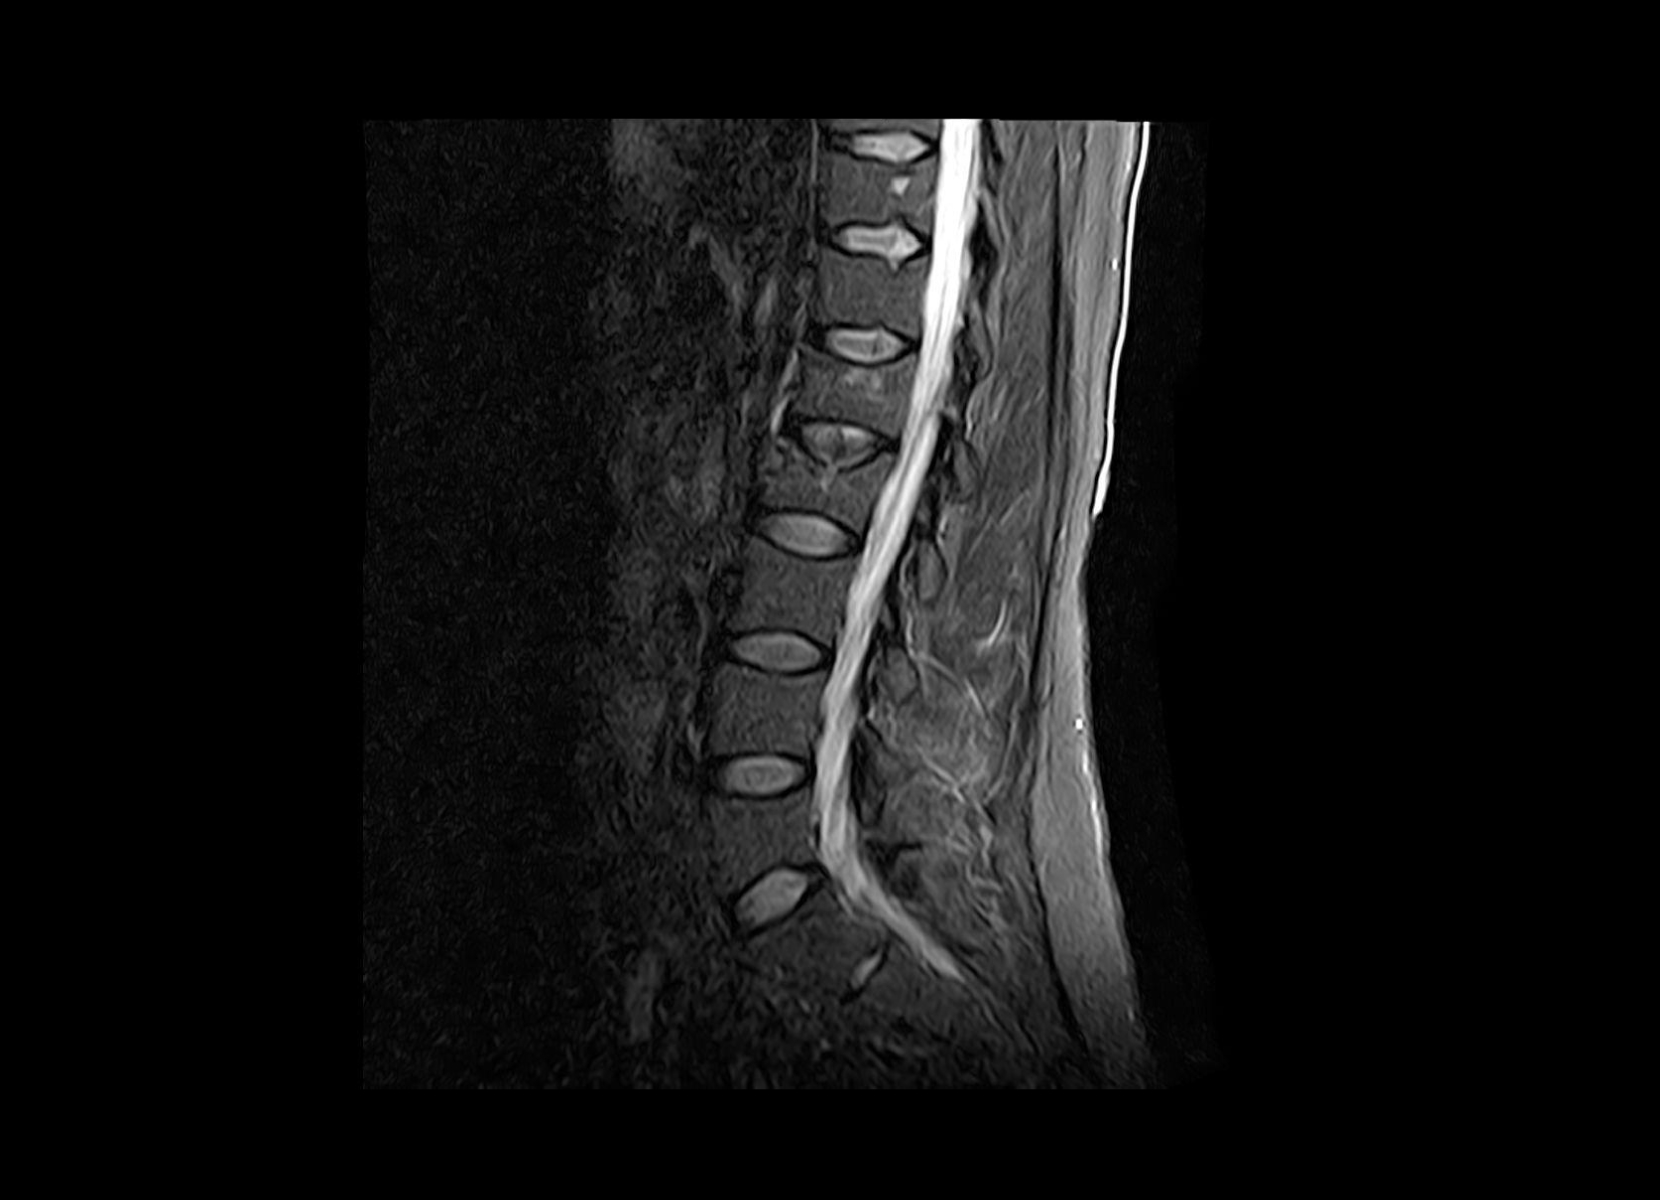

Conventional

STIR

SubtleSYNTH™

(Synthesized STIR)™

Trauma

GE 1.5T

C-spine